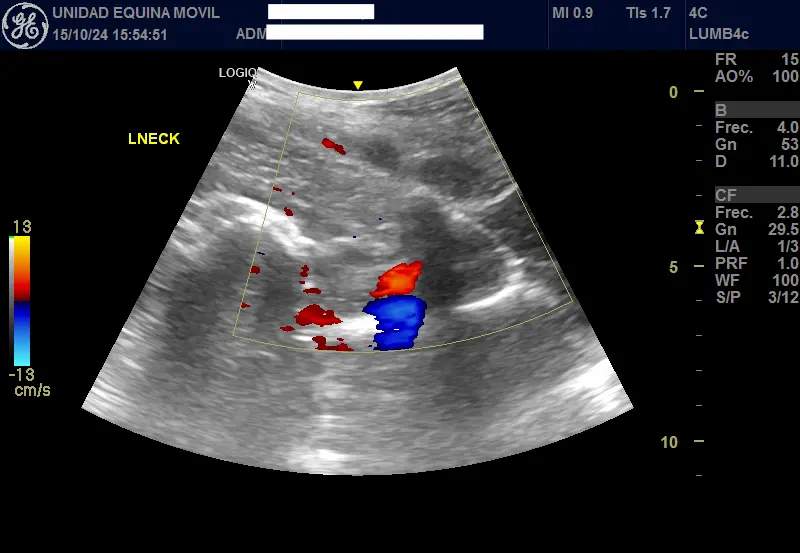

Advanced Diagnostic Imaging

We carry out diagnostic tests such as scintigraphy, magnetic resonance imaging, among others, in collaboration with equine veterinary hospitals.